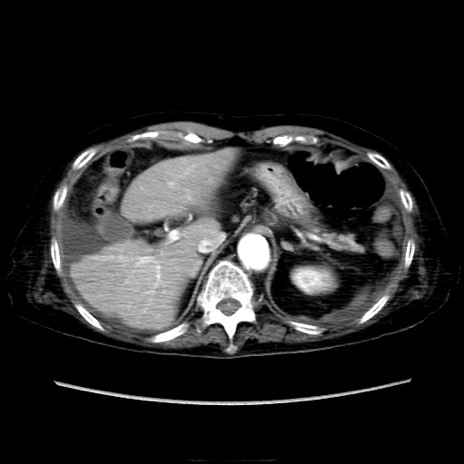

症例40(横断像)

【症例】90歳代女性

【主訴】腹痛・嘔吐

【現病歴】 食欲低下、嘔吐があり昨日他院受診。肺炎と診断され入院となる。入院後より腹部全体に圧痛あり。胃管留置され経過みていたが、症状持続するため、

当院転院となる。

【既往歴】胸椎圧迫骨折、胆石症

【身体所見】腹部:中央に激痛あり、圧痛あり、反跳痛不明

【データ】WBC 17100、CRP 18.82

横断像